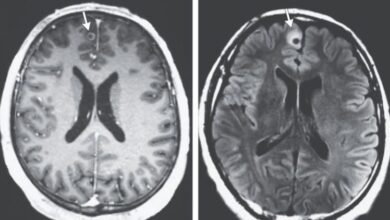

Homem tinha uma tênia viva há décadas no cérebro

Um homem internado com confusão mental e convulsões, nos Estados Unidos, descobriu que tinha uma tênia viva no cérebro há…